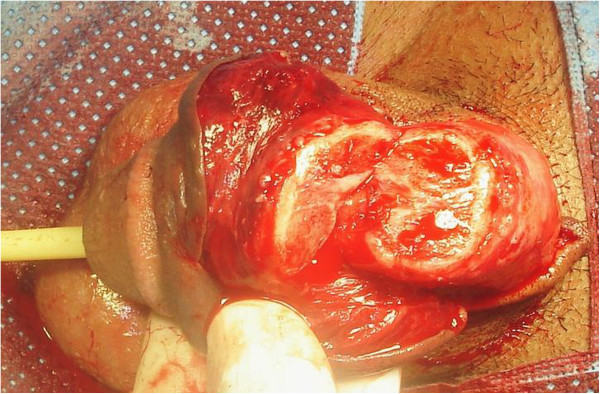

阴茎切除标本剖面图

阴茎剖面图像分析